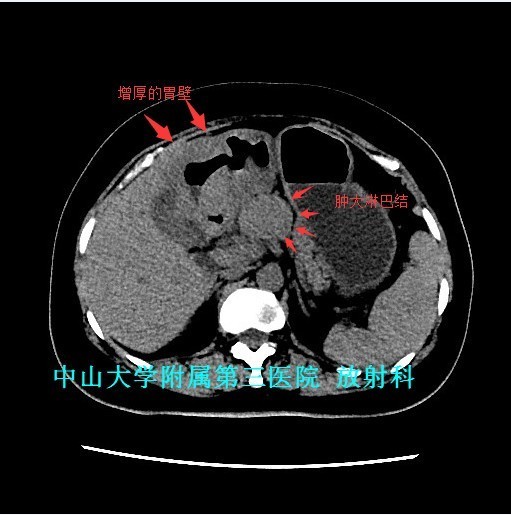

查体:腹软,上腹部轻压痛、无反跳痛,未触及包块。 辅查:1、胃镜:胃十二指肠恶性病变(待病理);2、上腹部CT:胃窦至十二指肠胃壁弥漫性增厚,考虑淋巴瘤可能性大。

讨论:原发性胃肠道淋巴瘤是一组起源于胃肠道黏膜下层淋巴组织的恶性肿瘤,成人较少见,约占胃肠道恶性肿瘤的1~4% 。影像表现具有一定特征性:弥漫性或局限性胃壁增厚是胃淋巴瘤主要特征,增厚的胃壁内缘呈波浪样或分叶状,外缘较光整,胃腔有一定的扩张度,增强扫描动脉期呈轻中度强化,静脉期持续强化。主要与胃癌鉴别,胃癌也表现为胃壁增厚,但一般增厚无淋巴瘤明显,而且胃壁僵硬,官腔变窄,常有浸润周围组织器官。 参考文献:侯明杰,齐鹏飞,高万勤等.原发胃肠道淋巴瘤的影像表现和误诊分析[J].实用放射学杂志,2014,(12):2112-2113,2121.